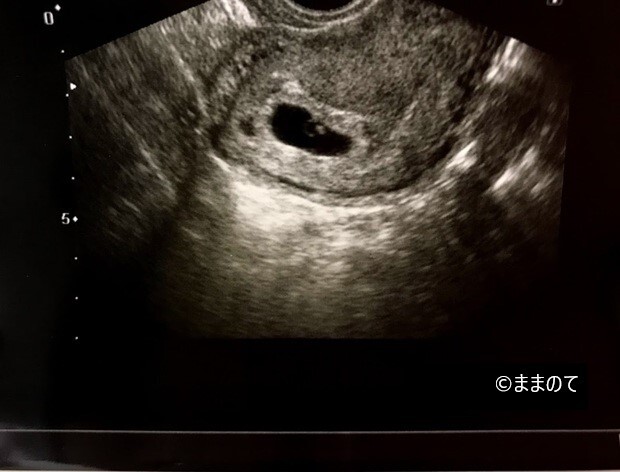

上の画像は、筆者が第二子妊娠を妊娠したときの6週2日の胎嚢です。うっすらと卵黄嚢らしきものが確認できます。写真からはサイズはわかりません。設備が古かったのか、医師の信条によるものなのかは定かではありませんが、とにかく手元にあるのはなかなかにさっぱりとしたエコー写真のみなのです。

第一子のときに健診を受けていた病院のエコー写真には、GSやCRL、BPDといったさまざまな数値がしっかりと明記されているのとは対照的です。

実は健診中も「胎嚢は何cmだよ」「赤ちゃんは何cmに育っているよ」と告げられたことはありません。診察室に用意された大小さまざまなキューピーちゃんの中から「今はこれくらいの大きさ」と示されるざっくり加減です。一度「数値を教えてください」とお願いしましたが、「誤差があるから意味ないよ」というひと言で終わりました。

二人目ということもあり、私自身も「待たなくて済むし元気ならば良いか」くらいの感覚だったため特に気にしていませんでしたが、健診で細かい数値を伝えてほしい場合は、医師の性格や使用している設備について、あらかじめ確認してから受診をした方が良いかもしれません。